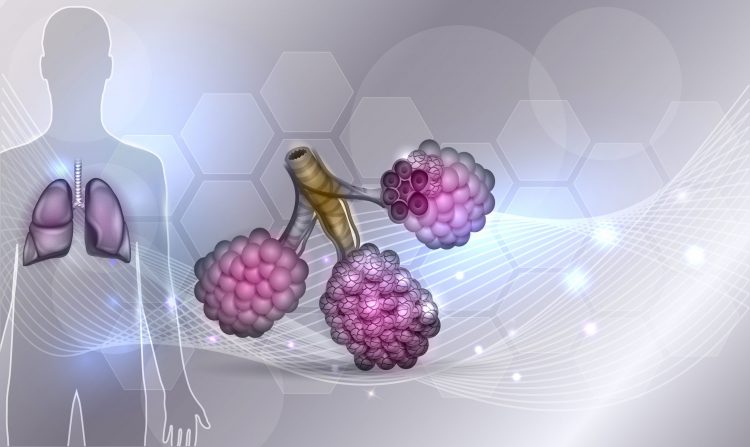

The European Commission and European Medicines Agency have approved the triple combination Kaftrio for use in certain cystic fibrosis patients, triggering the drug to be accessible on the UK’s National Health Service.